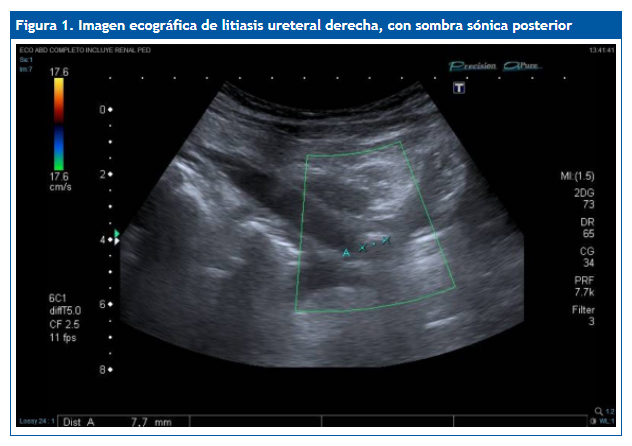

Ante los vómitos y la exploración abdominal se solicitaron: sedimento de orina pH 5, densidad 1030, hematíes 150/µl, proteínas 75 mg/dl, uratos amorfos; hemograma normal; química (función renal, proteínas totales, albúmina, electrolitos incluyendo Na, K, Cl, Ca, Mg, fósforo) normal; urinocultivo negativo; coprocultivo y virus en heces negativo; radiografía de abdomen normal, no se visualiza imagen de litiasis; ecografía abdominal (Figs. 1 y 2): cálculo de 7-8 mm, casi en el meato ureteral derecho, a 5-6 mm de la vejiga, con moderada ureterohidronefrosis proximal. No había líquido libre intraperitoneal. No se observa apéndice engrosado. El riñón y la vía excretora urinaria izquierdos no mostraban alteraciones.

La ecografía ha supuesto un gran avance en el diagnóstico de los cálculos, especialmente en niños, en los que suelen ser de pequeño tamaño. El aspecto típico es el de una imagen hiperecogénica con sombra sónica posterior.